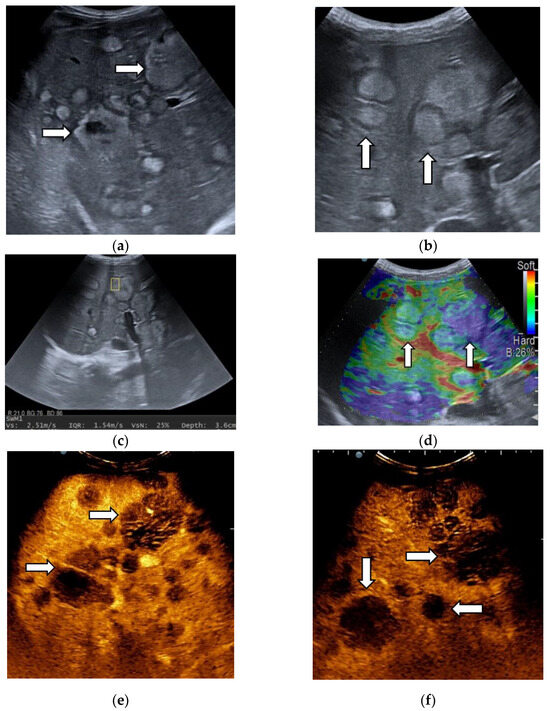

3.2. Contrast-Enhanced Ultrasound

3.3. Shear Wave Measurements in Liver Tumors

3.4. Real-Time Tissue Elastography